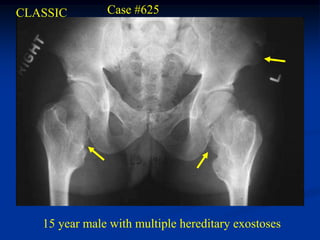

CLASSIC        Case #625

15 year male with multiple hereditary exostoses

Tibia and fibula

Lateral view